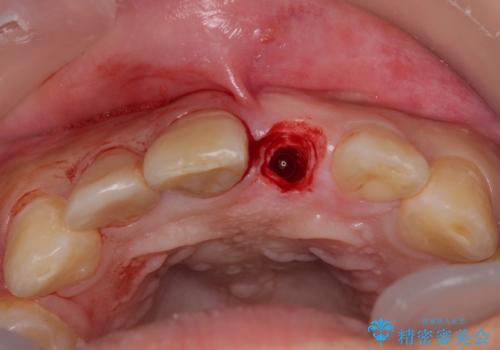

骨量は十分にあったため、インプラント埋入後速やかに仮歯を装着して、歯肉治癒後にオールセラミッククラウンによる補綴治療を行うこととしました。

日中は仮歯の着いた床タイプのリテーナーを装着していていましたが、仮歯が装着された段階でマウスピースタイプのリテーナーに変更しました。

セラミックで自然な口元となり、視線が集まっていたことも気にならなくなったとのことでした。